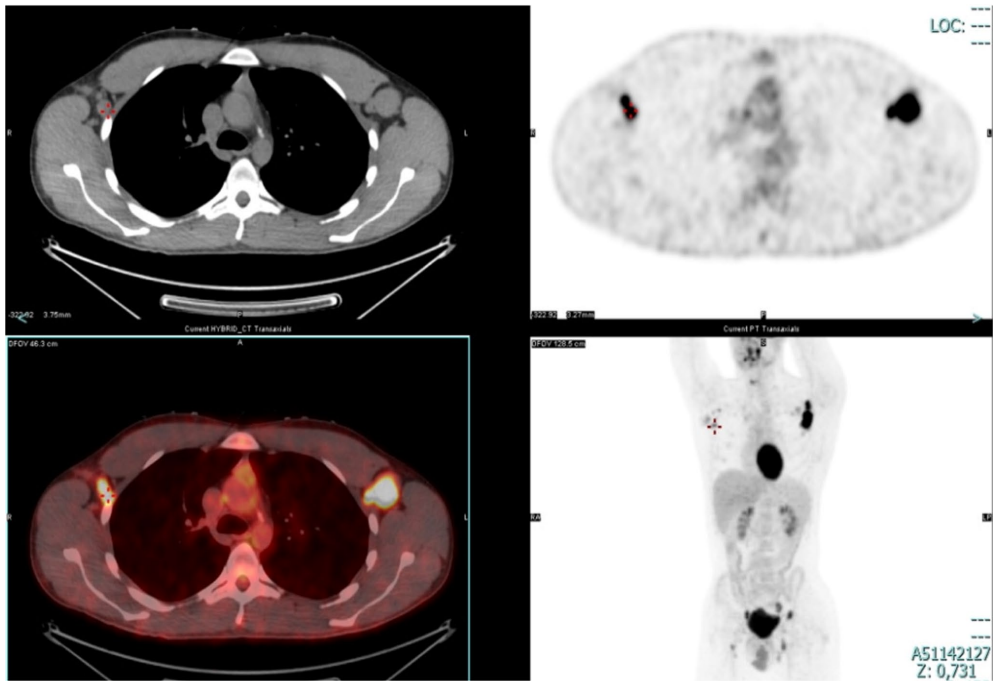

IEI与淋巴瘤:约15%的CVID患者伴淋巴增殖,NFKB1/TACI突变更易进展为淋巴瘤。机制涉及BCR repertoire受限、DNA修复缺陷等。推荐对IEI患者定期监测淋巴组织,PET-CT等影像学评估(如图3显示SUV值15的代谢亢进淋巴结)可辅助识别恶性转化。